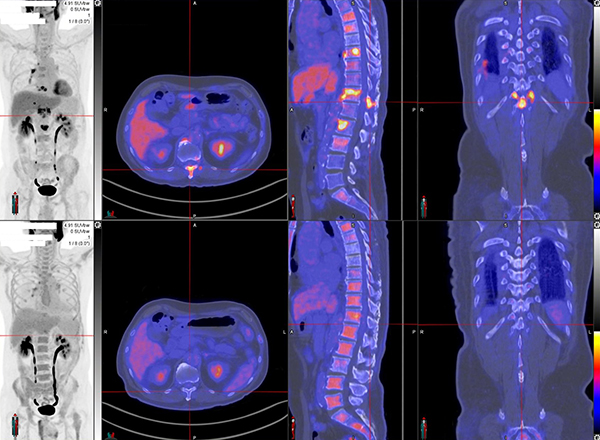

脑神经内分泌肿瘤

双示踪剂PET/CT (F-18 FDG及Ga-68 DOTATATE) 用於评估脑神经内分泌肿瘤体内的扩散情况

![]() [F-18] FDG |

![]() [Ga-68] DOTATATE |